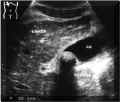

Examination

of

gallbladder

revealed

a

large

(2,2cm),

echogenic,

intraluminal

mass

with

smooth

surface.

broad

acoustic

shadow,

posterior

to

the

was

present.

wall

thin.

ANSWER:

Single

gallstone

in

gallbladder.